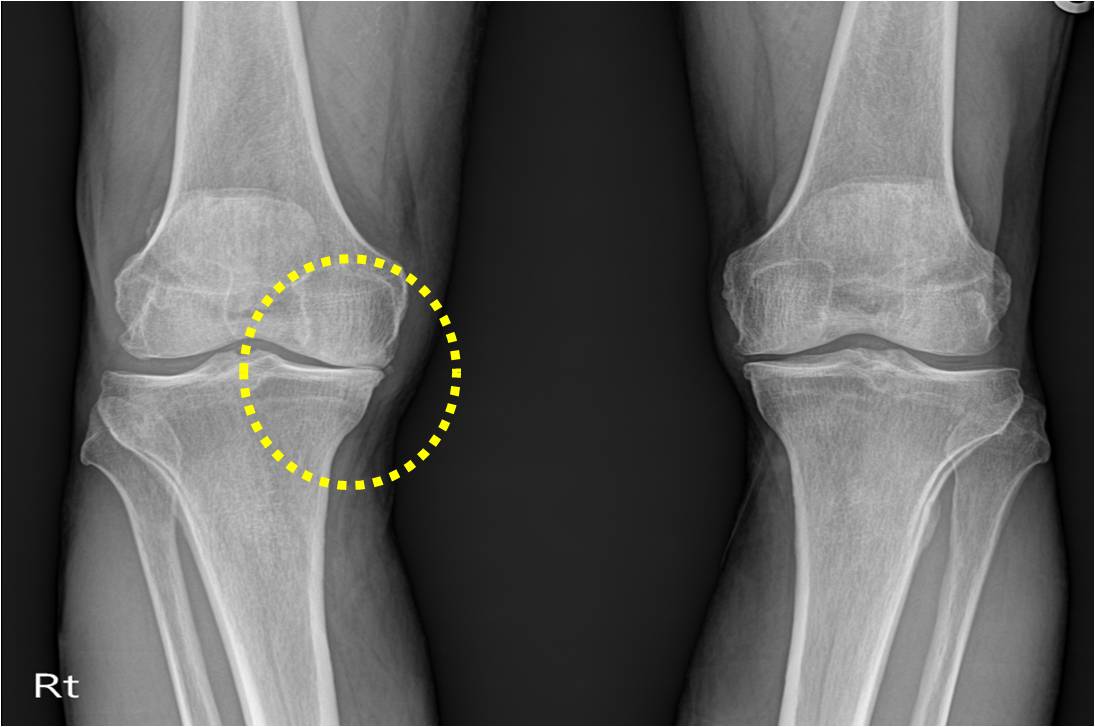

MSM의 효능 1. 관절건강

MSM의 유황성분은 우리 몸의 면역체계에 영향을 미쳐 세포 활동을 촉진시키는 방식으로 항염증제 역할을 하게 됩니다. 관절염, 건염, 요통, 근육경련에 효과가 좋다고 합니다. 단백질 구조를 형성하여 뼈, 근육을 구성하는데 기여하며 관절 부종이나 경직을 일으키는 염증 반응을 낮추는데도 도움이 되어 관절의 통증을 줄여주는데 많은 도움을 줍니다.